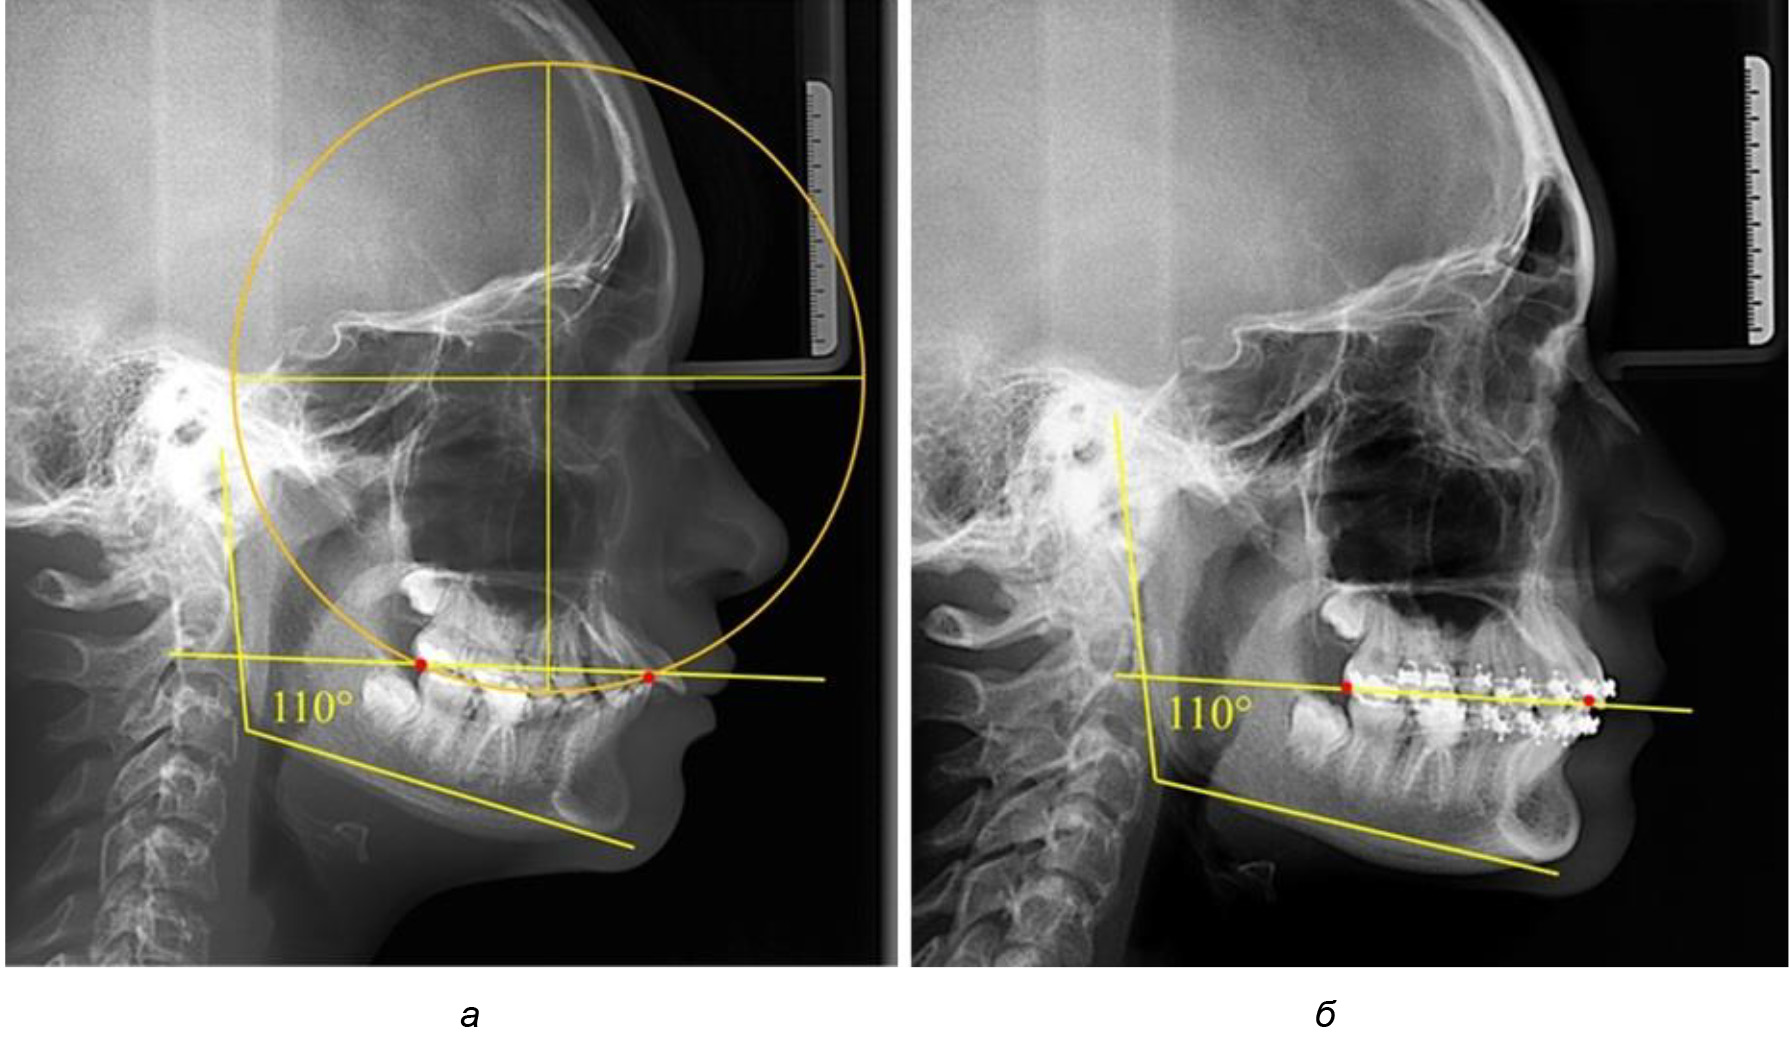

При анализе латеральных ТРГ устанавливали реперный окклюзионные точки в переднем и боковом отделе. Передняя точка устанавливалась на режущем крае нижнего медиального резца, которую в клинике ортодонтии обозначают как vPOcP. Дистальная точка второго нижнего моляра обозначалась как hPOcP. Измеряли расстояние между окклюзионными точками, что определяло сагиттальный размер окклюзионной линии. Использование программ PowerPoint позволило проводить окружность, проходящую по линии смыкания зубов через окклюзионные точки. Измеряли радиус окружности. Учитывая вариабельность размеров окклюзионной линии и радиуса окружности, определяли относительный показатель через отношение радиуса круга к длине сагиттального размера окклюзионной линии. Глубину окклюзионной кривой измеряли от точки наибольшей выпуклости до окклюзионной линии (рис. 1). На ортопантомограмме (ОПТГ) также соединяли окклюзионные точки правой и левой стороны и измеряли глубину окклюзионной кривой от точки наибольшей выпуклости до окклюзионной прямой линии. Результаты глубины кривой Spee сравнивали по данным ТРГ и ОПТГ.

Рис. 1. Метод определения кривой Spee на ТРГ (а) и на ОПТГ (б)

Анализ результатов показал, что глубина кривой Spee в среднем по подгруппе составил (4,12 ± 0,53) мм как при анализе ТРГ, так и ОПТГ.

Деление величины радиуса круга к длине окклюзионной линии составило 1,623 ± 0,02. Таким образом, для определения радиуса окружности, соответствующей кривизне окклюзионного контура боковой ТРГ, необходимо измерить расстояние между передней и задней окклюзионными точками и последующим умножением полученной величины на число Фибоначчи (рис. 2).